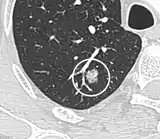

Spiculated lung nodule.[9]

- Margin morphology: a spiculated margin is a risk factor for cancer.[8] Benign causes tend to have a well defined border, whereas lobulated lesions or those with an irregular margin extending into the neighbouring tissue tend to be malignant.[10] In particular, spiculations are highly predictive of malignancy with a positive predictive value up to 90%.[9] Also, a "notch sign", which is an abrupt indentation of the nodule, increases the risk of cancer, but may also be found in granulomatous diseases.[9]